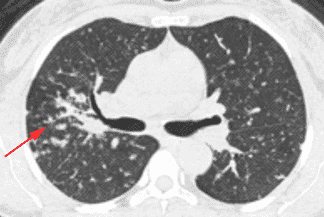

Texto alternativo para a imagem Figuras 1, 2, 3, 4 e 5. Créditos: Dra. Elazir Mota - Rio de Janeiro/RJ

Descrição das figuras 1, 2, 3, 4 e 5: Tomografia computadorizada do tórax com cortes axiais evidenciando pequenos nódulos distribuídos principalmente ao longo dos brônquios e vasos pulmonares (setas vermelhas). Nos cortes coronal e sagital observa-se o predomínio das anormalidades descritas nas regiões superiores e médias, de localização mais central.

• As alterações pulmonares predominam nas regiões centrais e lobos superiores, sendo geralmente bilaterais e simétricas. Predominam os pequenos nódulos sólidos com distribuição perilinfática, ou seja, ao longo dos brônquios, septos interlobulares, vasos pulmonares e regiões subpleurais. Lesões nodulares escavadas e derrame pleural são raros na doença;